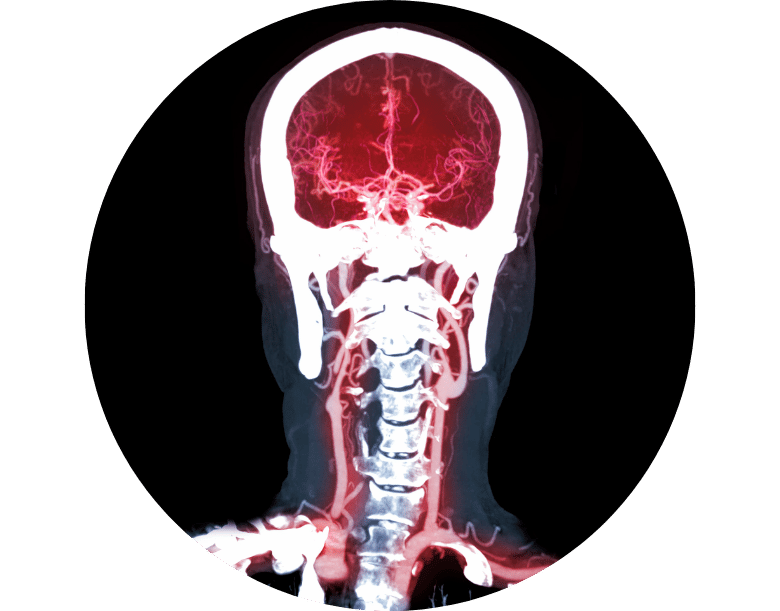

Beyin Anevrizması Nasıl Teşhis Edilir?

Anevrizma tanısı için gelişmiş görüntüleme yöntemleri kullanılır:

-

BT anjiyografi (Bilgisayarlı Tomografi)

MR anjiyografi

Klasik beyin anjiyografisi (DSA)

Bu testler, anevrizmanın konumunu, büyüklüğünü ve kanama olup olmadığını net şekilde gösterir.

Erken teşhis, yırtılmadan önce önlem alınmasını sağlar.